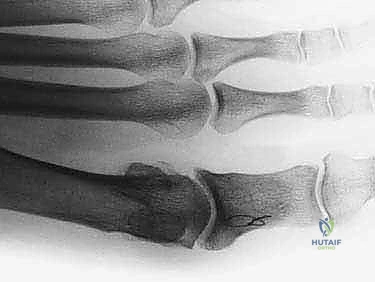

- التصوير بالأشعة السينية (X-rays): يتم أخذ صور بأوضاع تحمل الوزن (Weight-bearing). هذا الإجراء أساسي لتحديد مرحلة المرض، وتقييم حجم النتوءات العظمية، وقياس المسافة المفصلية المتبقية.

1. عملية شايليكتومي (Cheilectomy): تنظيف المفصل

كلمة "Cheilos" تعني باليونانية "الشفة"، وتشير إلى النتوء العظمي (الشفة العظمية) الذي يتكون على حافة المفصل. تتضمن هذه العملية الإزالة الجراحية الدقيقة للنتوءات العظمية الظهرية (العلوية) والجانبية من رأس المشط الأول وقاعدة السلامية القريبة.

الهدف: إزالة العائق الميكانيكي الذي يمنع المفصل من الانثناء لأعلى، وتخفيف الضغط المباشر على الأنسجة والأحذية. عادة ما يتم استئصال حوالي 30% من الجزء الظهري لرأس المشط للوصول إلى غضروف صحي.

بمجرد كشف المفصل، يتم تقييم حجم الضرر الغضروفي. باستخدام منشار جراحي دقيق متذبذب (Oscillating saw) وأزاميل دقيقة، يقوم الدكتور هطيف بإزالة النتوءات العظمية الظهرية والجانبية من رأس المشط والسلامية القريبة. يتم استئصال حوالي 20% إلى 30% من الرأس الظهري للمشط حتى يتم الوصول إلى حافة الغضروف الصحي المتبقي. يتم بعد ذلك تنعيم الحواف العظمية بمبرد خاص لمنع أي احتكاك مستقبلي.